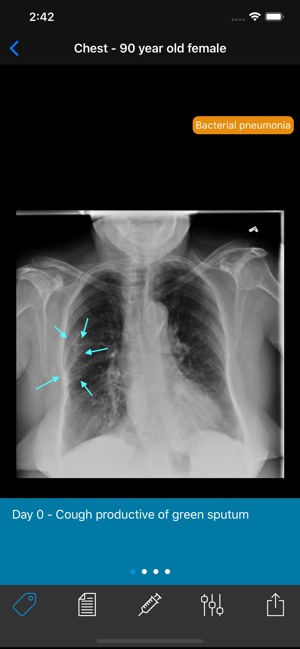

• Real cases with reports, diagnoses, management, and follow-up studies

• Pathologies including fractures, dislocations, infectious disease, cardiopulmonary disease, gastroenterological disease, and many more

• Review x-rays by adjusting brightness, contrast, and zoom